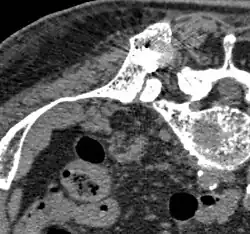

Vor der RFA: Hinterer oberer Darmbeindorn (Spina iliaca posterior superior) mit osteolytischer Metastase (ca. 2 cm im Durchmesser, siehe Pfeile) -

Während der RFA: A) Die HF-Elektrode wurde direkt in die Knochenmetastase geführt. B) Nach der Ablation wurde eine Mischung aus Knochenzement und Bariumsulfat in den entstandenen Freiraum injiziert. -

Nach der RFA: Die Verteilung des Knochenzementes in dem nach der Ablation entstandenen Hohlraum ist zu erkennen.